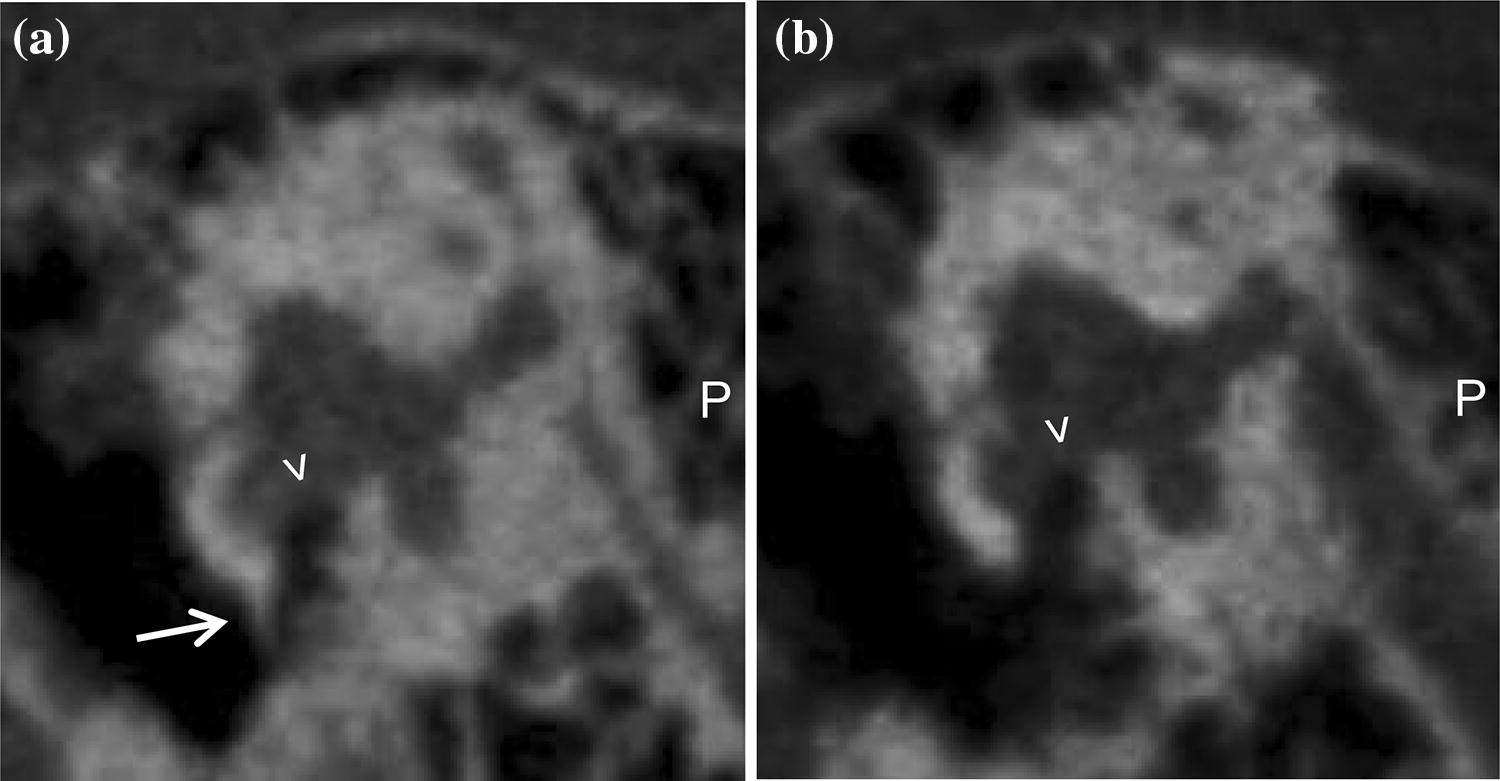

Bony overhangs at the RWN were clearly visualized in seven cases (26%, Fig. 3). Granulation tissue inside the RWN, not allowing to identify the round window membrane (RWM), was found in four cases (15%, Fig. 4a). In all other 23 cases (85%) the RWM was clearly visible. Additional soft tissue inside the oval window niche was seen in four cases (15%, Fig. 4b). In one case (4%) it was possible to describe an additional, secondary RWM (Fig. 5). Regarding these 108 radiologically ‘tiny’ items the neuro-radiologist was not able to make a clear decision in nine cases (8%).

Fig. 3

Sagittal slices of temporal bone CBCT. The RWN ( >) can be clearly identified on the right (a) and on the left (b) patient side. On the right side there is an additional bony overhang ( →), while the left side seems open